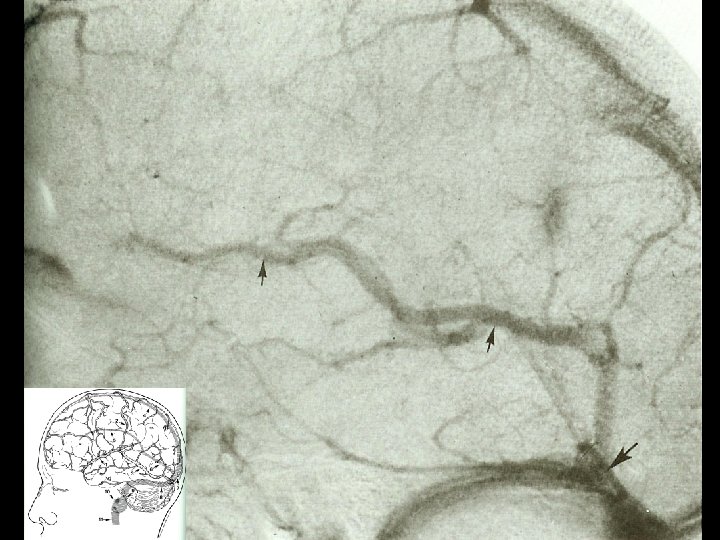

Angiographic digression to aid the understanding of venous angiography Michigan Neurosurgery

Capillary phase Michigan Neurosurgery